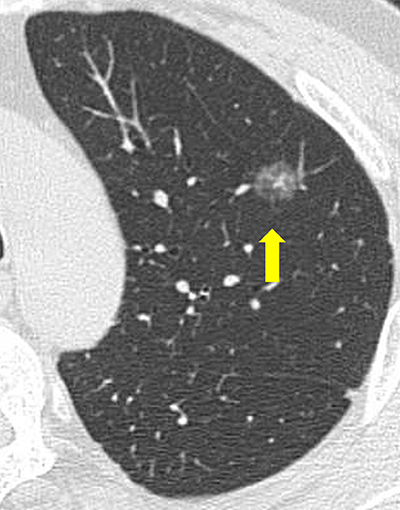

CTで発見されるすりガラス影病変の経過観察

近年、CT検診の普及などにより、通常のレントゲンでは発見できない淡いスリガラス結節(図4)が発見されることが多くなりました。小さなスリガラス影は経過をみても変化を示さないものが多いのですが、一部では数年の経過で増大傾向を示す切除が必要な肺癌を含んでいます。当センターでは最新のヘリカルCTを使用し、CT検査による被曝線量も考慮し、適切な経過観察および手術療法を行っています。